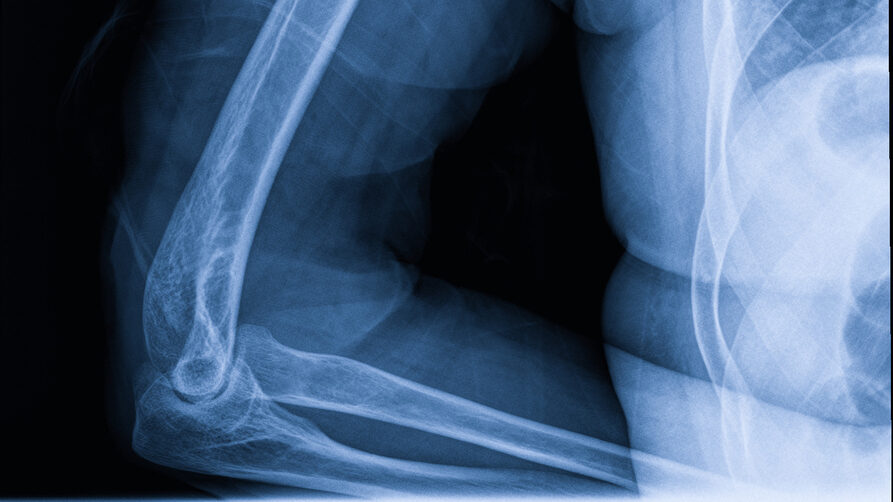

Distal Humerus Fractures of the Elbow

Distal humerus fractures are breaks in the lower portion of the upper arm bone near the elbow, causing pain, swelling, and reduced mobility. These fractures can affect elbow stability and function, making everyday activities like bending or lifting difficult. The severity of the fracture determines the treatment approach, which may include immobilization, rehabilitation, or surgery to restore strength and range of motion.

Distal humerus fractures typically result from high-impact trauma, such as falls, car accidents, or sports-related injuries. In older adults, even minor falls can lead to fractures if the bones are weakened by conditions like osteoporosis. These fractures can also occur from sudden twisting or forceful impact to the elbow, making both accidental injuries and age-related bone fragility important contributing factors.